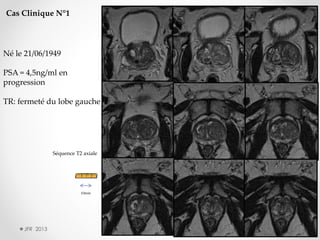

Cas Clinique N°1

Né le 21/06/1949

PSA = 4,5ng/ml en

progression

TR: fermeté du lobe gauche

Séquence T2 axiale